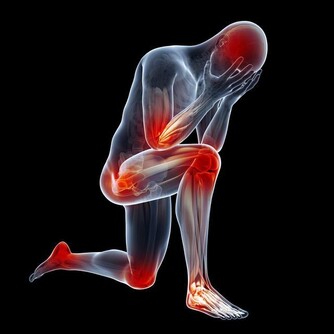

人體缺乏鈣質時,其實害怕的是血液含鈣量不足,以致於影響身體機能,醫學上稱為低血鈣症,它從神經的傳導訊息到內分泌,甚至是肌肉收縮都有關係。通常低血鈣症會影響三種肌肉:

骨骼肌:缺鈣會讓人肌肉緊繃,無法放鬆。

平滑肌:缺鈣時心臟會亂跳,反而會心律不整,有時可會導致猝死問題。

心肌:與腸胃道的蠕動跟吸收及血管有關,會影響血管收縮。